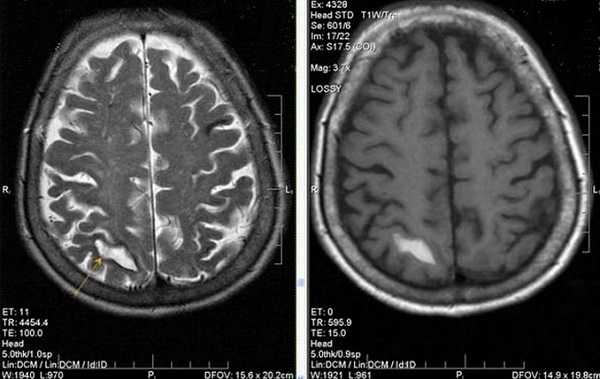

На PD/T2WI и FLAIR выглядит гиперинтенсивно. На PD/T2WI и FLAIR последовательностях возможно диагностировать до 80% инфарктов впервые 24 часа, но впервые 2-4 часа после инсульта изображение также может быть неоднозначным. На PD/T2WI и FLAIR продемонстрировано гиперинтенсивность в районе левой средней мозговой артерии. Обратите внимание на вовлечение в процесс лентиформного ядра и островковой доли. Область с гиперинтенсивным сигналом на PD/T2WI и FLAIR соответствует гиподенсивной области на КТ, что в свою очередь прямой признак гибели клеток мозга.

Псевдо-улучшение наблюдается на 10-15 день. Слева показана норма на DWI. На T2WI там могут быть гиперинтенсивная область в правой затылочной доле в сосудистой территории задней мозговой артерии. В T1WI после введения контрастного препарата на основе гадолиния визуализируется повышение сигнала (зона инфаркта указана стрелкой).